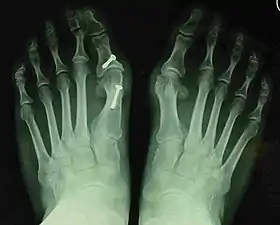

Bunion (hallux valgus) deformity is actually part of a complex of anatomical derangements of protruding mass (bunion), buckling of big toe (hallux valgus) and the bone behind it (metatarsus primus varus), displaced sesamoid bones (detrimental to the important walking function of big toe), collapsed metatarsal arch and several other secondary changes that are the domino effects of metatarsal primus varus. Thus, metatarsus primus varus correction has become the primary objective of all bunion surgeries.

Primus varus deformity is the leaning of the first metatarsal bone away from the second metatarsal and towards the opposite foot (Fig. 1). As it leans over, its head sticks out to form the bunion bump and it also widens the forefoot to cause shoes feeling too tight. Thus when bunion pain becomes unmanageable, surgical correction is to narrow the forefoot by repositioning of the first metatarsal head back to its normal position. This can be done by osteotomy (bone-breaking), soft tissue (non-osteotomy) or fusion techniques.

Syndesmosis procedure addresses specifically the two fundamental problems of metatarsus primus varus deformity that gives rise to the bunion deformity. They are leaning and instability of the first metatarsal bone . Syndesmosis procedure uprights the leaning first metatarsal bone with strong binding sutures between it and the second metatarsal bone (Fig. 2) and then also stabilizes it uniquely by creating a fibrous connecting bridge between these two bones (Fig. 3, 4). First metatarsal bone can be readily realigned because by definition of the metatarsus primus varus deformity its first metatarsal is abnormally loose and mobile.